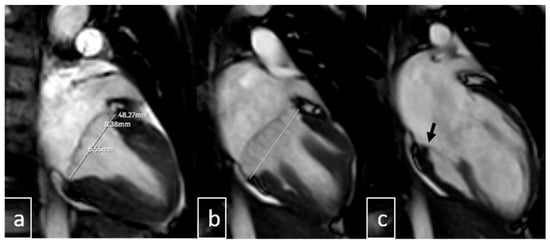

2.4. Image Analysis

3.6. Cardiac MRI Findings in MAD

3.10. Additional Imaging Findings